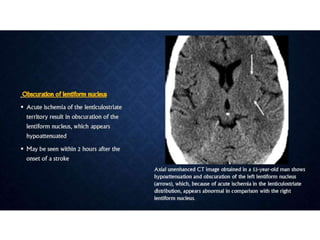

• 43.

ACUTE STROKE IMAGINGPROTOCOL • When acute stroke patients present within 6 hours of the onset of symptoms - un-enhanced CT or with conventional/MR imaging. • Hemorrhage at unenhanced CT or >1/3 MCA territory - not treated with thrombolytic drugs. • Ischemia of < 1/3 MCA territory, those who present <3 hours after the onset of acute stroke - intravenous thrombolytic drugs • 3–6 hours after the onset of symptoms - CT angiography and CT perfusion imaging to assess the intracranial and neck vessels and detect any penumbra. • Intraarterial therapy is usually considered for patients in whom a penumbra is seen. • Patients in whom no penumbra is seen are not usually treated with thrombolytic drugs